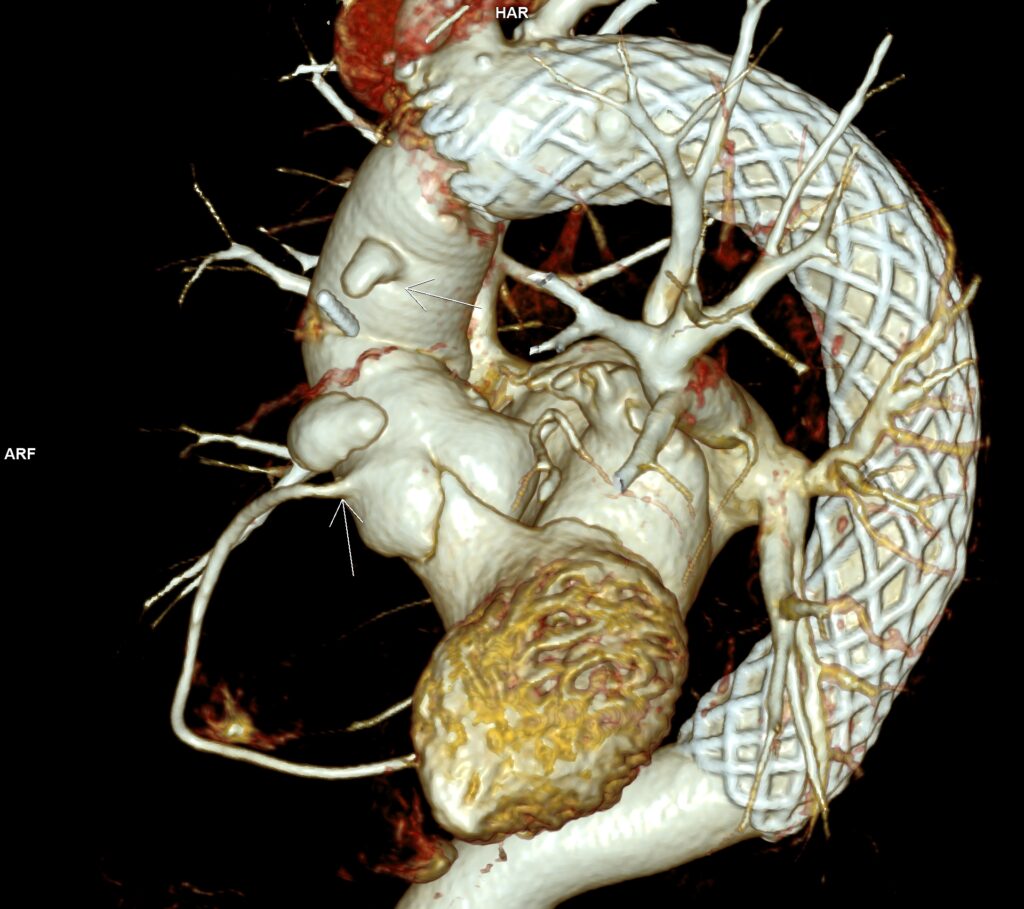

Figura 3: Reconstrucţie VRT din achiziţie angioCT toracică cu evidenţierea anevrismelor formate la inserţia inferioară şi superioară ale a protezei de aortă ascendentă

Pacient cunoscut cu proteză de aorta ascendentă și proteză endoaortică pentru dilatație anevrismală a aortei ascendente și descendente toracice, efectuează examinare angioCT pentru control postoperator. Se evidențiază câte o dezvoltare anevrismală la inserțiile inferioară și superioară ale protezei de aortă ascendentă și proteză metalică endoaortică de aorta descendentă în poziție normală. Incidental se evidențiază un fald de disecție în segmentul proximal al arterei carotide comune stâng cu ambele lumene circulante.